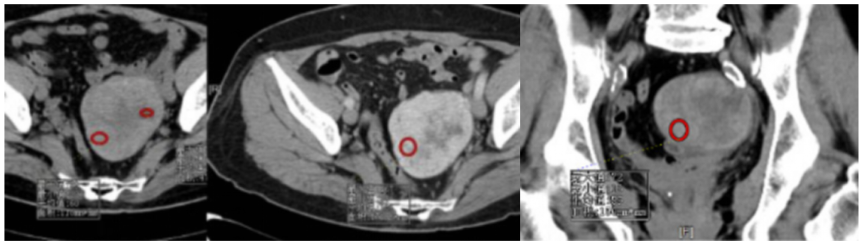

影像表现:子宫右后方见卵圆形软组织肿块影,与子宫后缘密切相连,病灶边缘清晰,病灶呈T1低信号T2低信号为主,其内夹杂少许散在斑片状T2高信号区,增强扫描病灶呈明显强化,与子宫肌层强化类似。盆腔未见明显肿大淋巴结,盆腔见片状压脂明显高信号影。

影像诊断:子宫浆膜下肌瘤。

CT表现:子宫增大,可呈分叶状表现。平扫肌瘤的密度可等于或略低于周围正常子宫肌层,增强检查肌瘤可有不同程度强化,多略低于正常子宫肌的强化。约10%子宫肌瘤发生钙化,主要见于绝经后退变的肌瘤。

MRI表现: 是发现和诊断子宫肌瘤最敏感的方法。在T1WI上,子宫肌瘤的信号强度类似子宫肌;然而在T2WI上,典型肌瘤呈明显低信号,边界清楚,与周围子宫肌信号形成鲜明对比。本例病灶与子宫后缘关系密切,病灶边缘清晰,T2呈较低信号,且增强呈明显强化,均符合较典型子宫肌瘤。